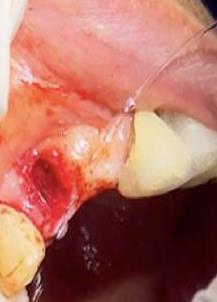

Sindesmotomía con un periostótomo de molt # 9, posteriormente se realizó la luxación con un elevador recto, buscando el punto de apoyo, seguido se efectuó la prensión con el fórceps 150 en el diente con sumo cuidado de no tocar la encía colocándolo hasta el cuello dental, haciendo movimientos de lateralidad y rotación hasta lograr la dilatación del alveolo, y finalmente la tracción del órgano dentario, observando que la raíz este integra, y que estructuras alrededor estén conservadas, de la misma forma se revisó el alveolo en busca de la presencia de granulomas o espículas óseas, una vez ya revisado se procedió al curetaje, con una cucharilla de lucas, se introdujo y se dio paso al retiro del exudado purulento, se realizó irrigación del alveolo con solución fisiológica, una vez limpio se realizó una sutura simple con sutura nylon, seda # 3/0 en el medio del alveolo con la finalidad de aproximar rebordes, evitar su contaminación por el ingreso de comida, además generar una mejor cicatrización en una zona estética , finalmente se aplicó presión por medio de una gasa que mordió el paciente por un lapso de 30 minutos, para contribuir con una hemostasia adecuada.

Figura 8. Irrigación del alveolo con solución fisiológica y sutura simple en la mitad del alveolo.

Elaboración: Los autores.